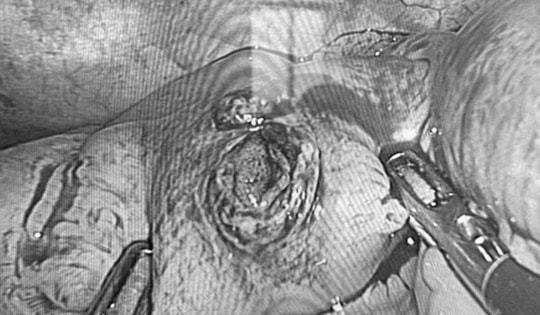

Phẫu thuật nội soi cấp cứu thành công cho nam thanh niên bị đinh xuyên thủng ruột non

Các bác sĩ Bệnh viện Hữu nghị Việt Nam–Cuba Đồng Hới đã phẫu thuật cấp cứu thành công một trường hợp là nam thanh niên bị súng bắn đinh bắn xuyên thành bụng, găm thủng ruột non trong lúc lao động.